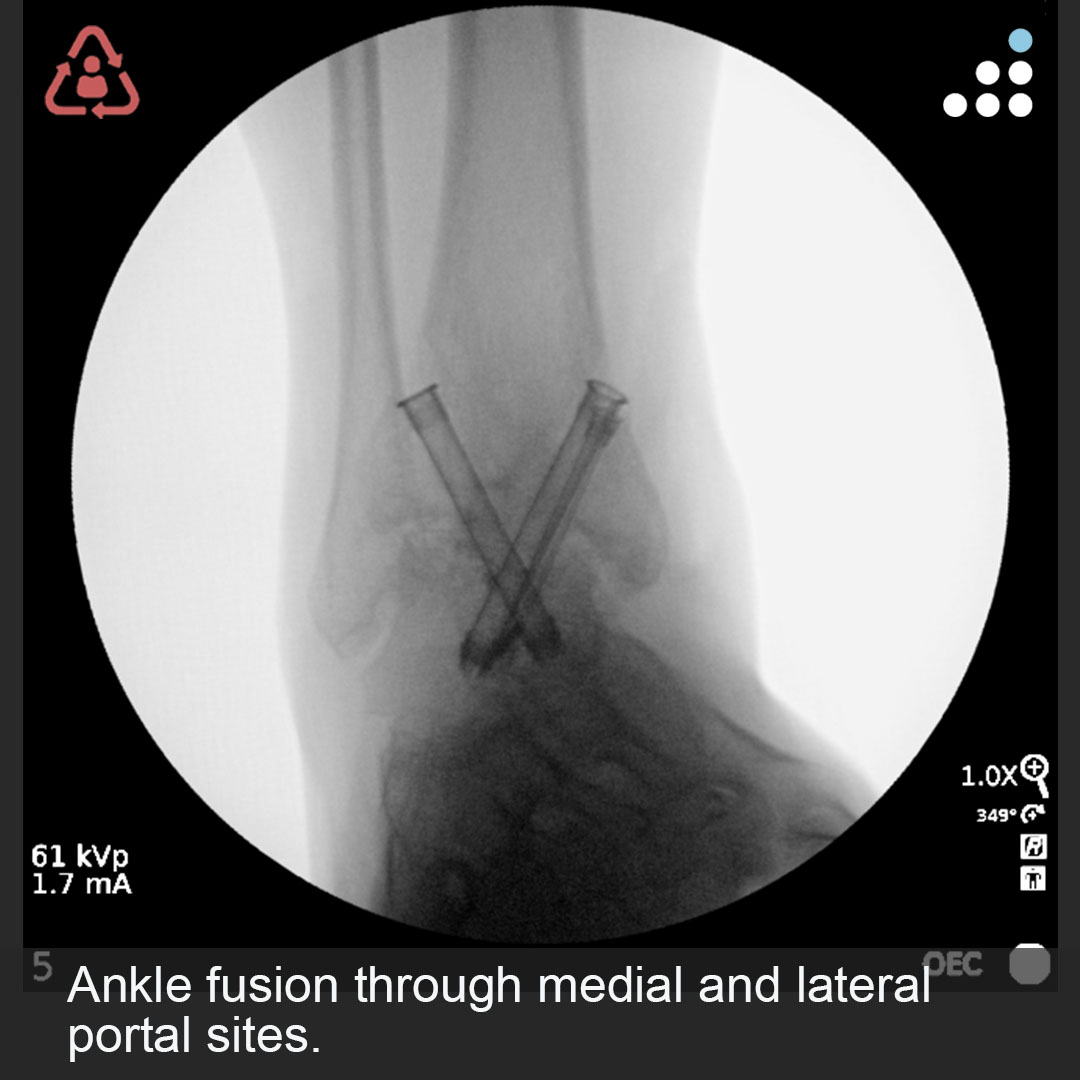

Here are intra-op & post-op images of yesterday's case by Dr. Jan Szatkowski(@orthotraumamd) & @IU_Health.

ANKLE PAIN 9 MONTHS S/P OPEN ANKLE FRACTURE-DISLOCATION IN 33M

Do you agree with the treatment? Why or why not?

Comment & keep the great conversation going!

#orthotwitter